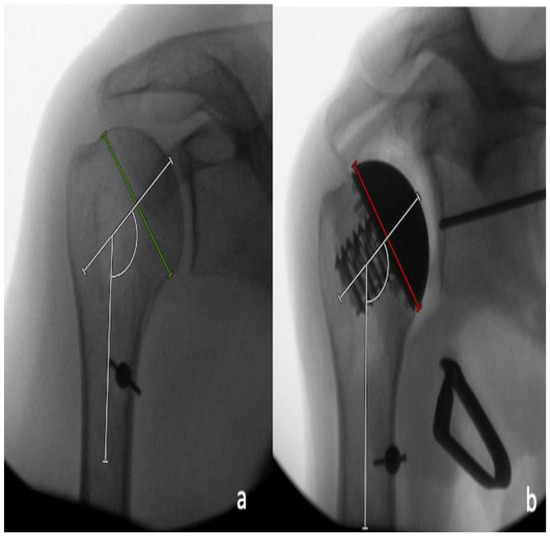

The pin positioning for the glenoid preparation was assessed in the supero-inferior and the antero-posterior directions by dividing the distance between the pin and inferior glenoid rim by the length of the glenoid, as well as the distance between the pin and the posterior glenoid rim and the width of the glenoid on the AP and the axillary radiographs, respectively (Figure 6a,b). These values were then displayed as percentages. In addition, the inclination and the version of the theoretical glenoid implantation were measured by determining the angle between the native glenoid surface and the glenoid guide pin on the AP and axillary radiographs, respectively (Figure 7a,b).

Figure 4. (a) Determination of the pre-operative neck-shaft angle between the line perpendicular to the anatomic neck axis (green line) and the intramedullary axis. (b) Determination of the post-operative neck-shaft angle between the line perpendicular to the backsurface of the trunion (red line) and the intramedullary axis.

Figure 6. Pin placement was determined (a) by dividing the distance of the pin to the inferior glenoid rim (yellow line) by the supero-inferior extent of the glenoid (blue line) on the AP radiographs, and (b) the distance of the pin to the posterior glenoid rim (yellow line) by the antero-posterior extent of the glenoid (blue line) on the axillary radiographs.

Figure 7. Measurements of theoretical glenoid component inclination (a) and version (b) by determining the angle between the native glenoid surface and the glenoid guide pin. A guide pin placed with more inclination or retroversion leads to a larger recorded angle.